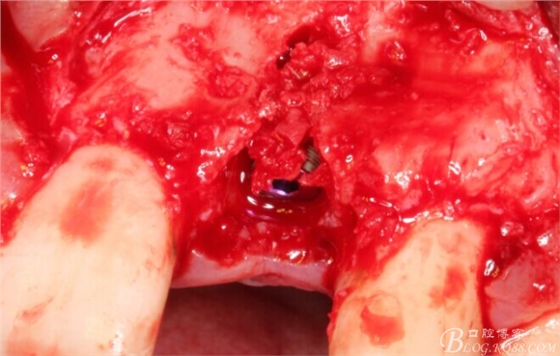

于是我果斷告知患者,手術(shù)失敗了,不能拖延,如不及時(shí)處理,炎癥繼續(xù)發(fā)展會(huì)很快波及鄰牙牙槽骨。患者接受我的建議。切開翻瓣,骨粉及生物膜消失了,骨吸收嚴(yán)重,幸運(yùn)的是,因?yàn)樘幚砑皶r(shí),鄰牙骨支持依然存在。

徹底掻刮。

有老師問我,為什么不在此時(shí)同期植骨同期植入植體?我的觀點(diǎn)是:不要一次做太多事情,做得越多風(fēng)險(xiǎn)越高。再說,此時(shí)軟組織不健康,沒有健康的軟組織如何能保證GBR的成功?所以,我僅放了一塊膠原蛋白就縫上了。